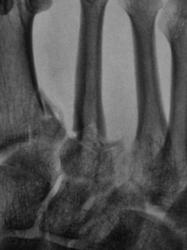

Неделю тому, пациент после ДТП был доставлен в рентгеновский кабинет. Было сделано много, в том числе был и заказан голеностопный сустав. Однако, в голеностопе патологии выявлено не было. Пациент находился в хирургическом отделении, и все, в принципе, нормально было, но вот предъявлял пациент жалобы на боли ... в стопе. Стопа отёкшая, болезненная при пальпации. Сегодня пациента направили на рентгенографию стопы с диагнозом...."Растяжение связок"..?

Произведена рентгенография в стандартных проекциях.

Вот, какие дела...с растяжением.

Хорошее растяжение,  вот только перелом основания 1,2 и 3 плюсневых костей не в счётМолчу-молчу!.

Молодец, хорошо косточки "растянул"